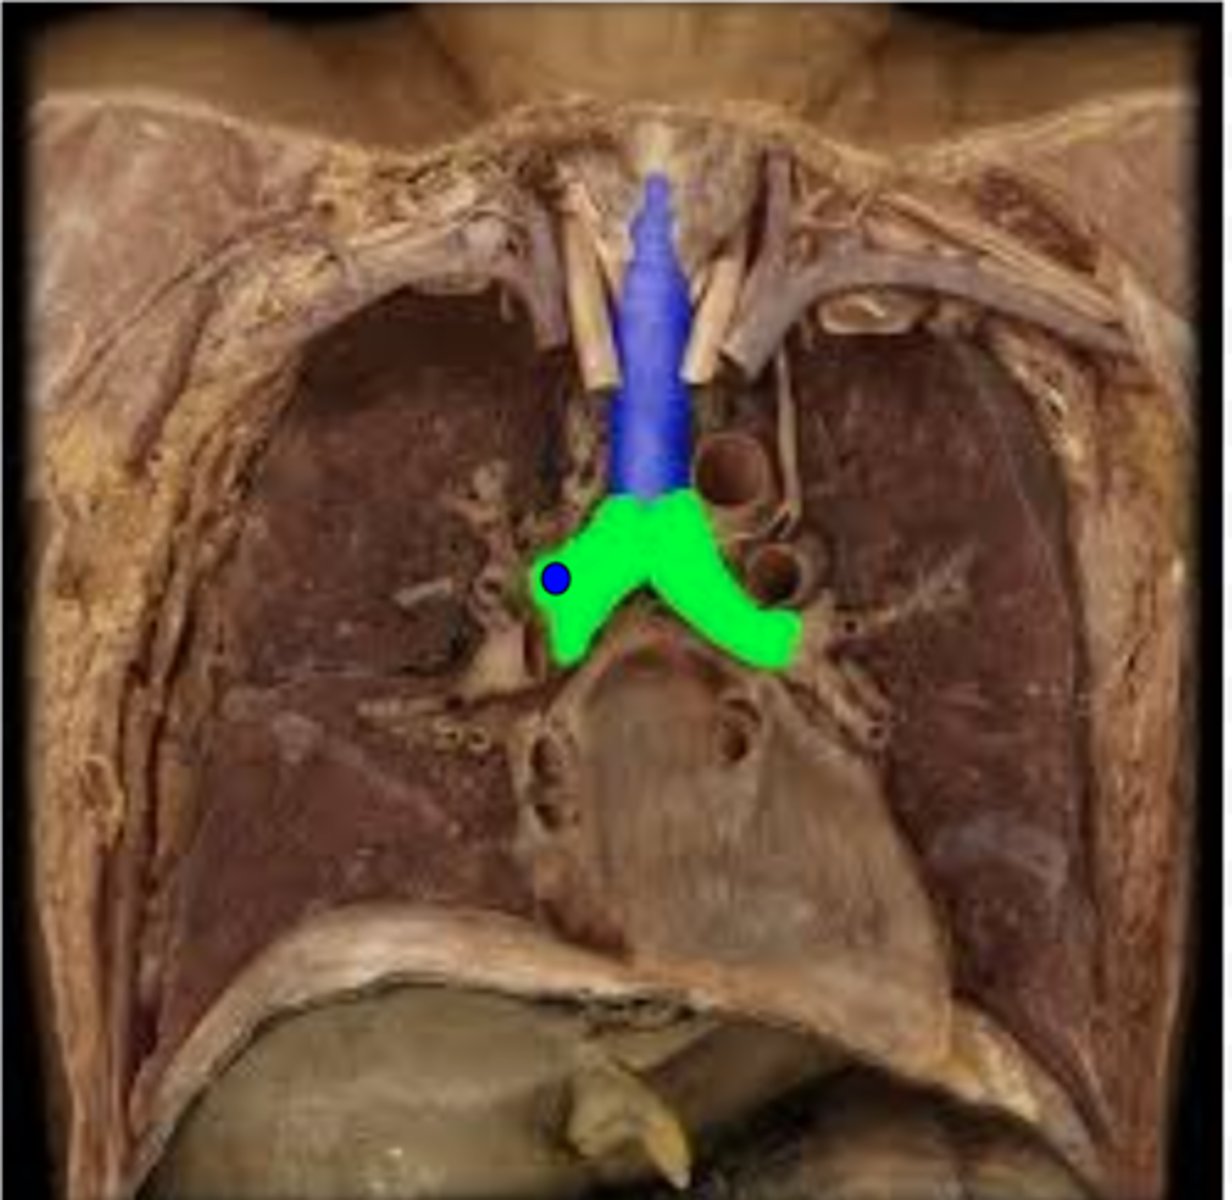

Trachea

Carina

Right Primary Bronchus

Left Primary Bronchus